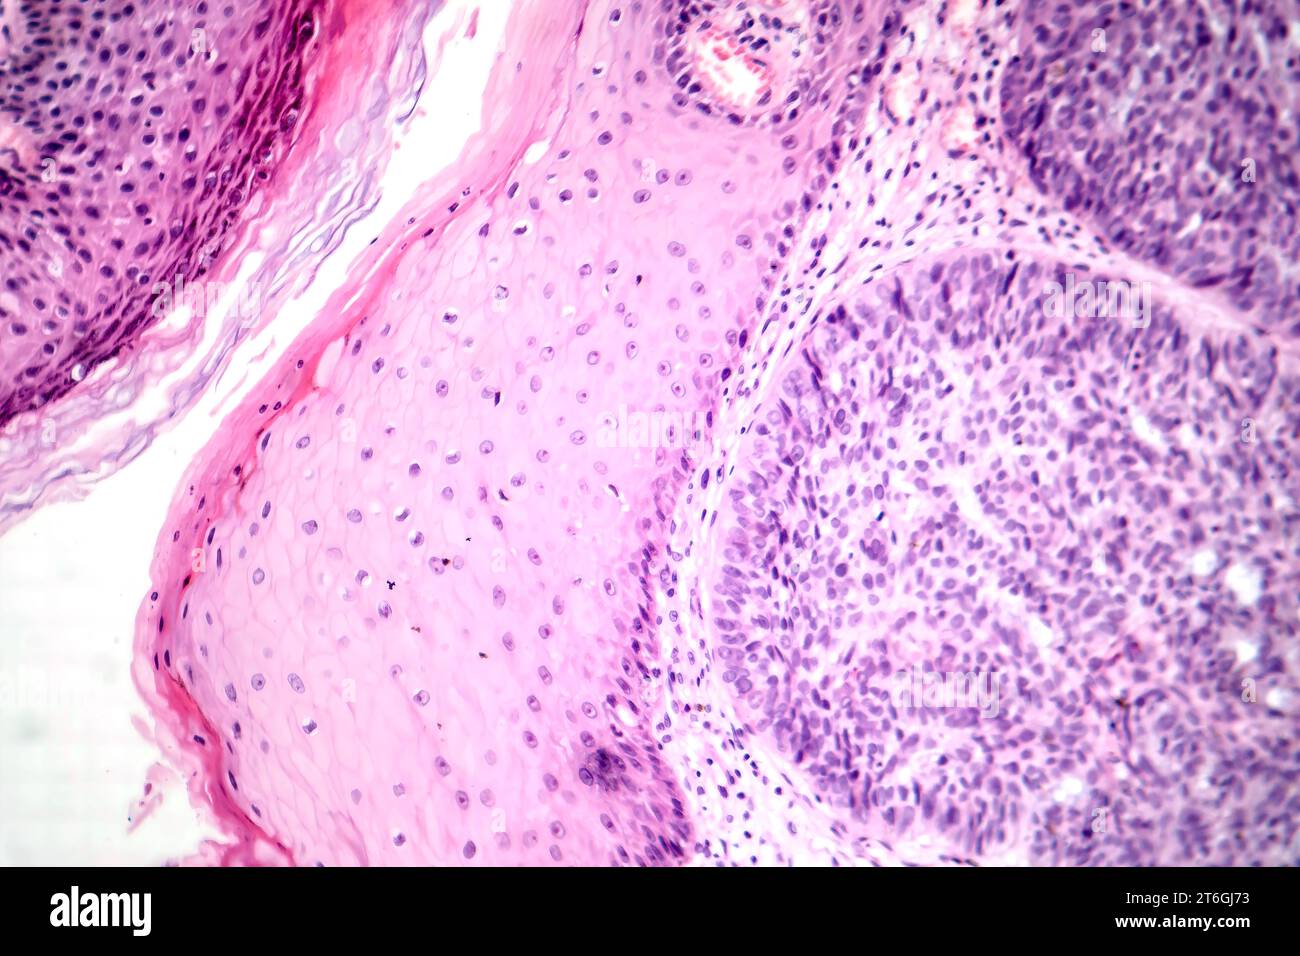

Basal Cell Cancer Cells. Sometimes, it can be mistaken for a harmless. basal cell carcinoma is a superficial, slowly growing papule or nodule that derives from certain epidermal cells. basal cell carcinoma (bcc, also called basal cell skin cancer, or just basal cell cancer) is most common type of skin cancer. basal cell carcinoma (bcc) is a type of skin cancer that can show up on the skin in many ways. the goal of treatment for basal cell carcinoma is to remove the cancer completely. Basal cell carcinomas arise from. Which treatment is best for. basal cell carcinoma is the most common form of skin cancer accounting for 90% of skin cancers in the. basal cell carcinoma is a type of skin cancer that causes a lump, bump or lesion to form on the outside layer of your skin. basal cell carcinoma (bcc) is the most common form of skin cancer and the most frequently occurring form of all cancers.

basal cell carcinoma is a superficial, slowly growing papule or nodule that derives from certain epidermal cells. basal cell carcinoma (bcc) is the most common form of skin cancer and the most frequently occurring form of all cancers. basal cell carcinoma is the most common form of skin cancer accounting for 90% of skin cancers in the. basal cell carcinoma (bcc, also called basal cell skin cancer, or just basal cell cancer) is most common type of skin cancer. basal cell carcinoma (bcc) is a type of skin cancer that can show up on the skin in many ways. basal cell carcinoma is a type of skin cancer that causes a lump, bump or lesion to form on the outside layer of your skin. Basal cell carcinomas arise from. Sometimes, it can be mistaken for a harmless. Which treatment is best for. the goal of treatment for basal cell carcinoma is to remove the cancer completely.

Basal Cell Cancer Cells basal cell carcinoma is a superficial, slowly growing papule or nodule that derives from certain epidermal cells. Sometimes, it can be mistaken for a harmless. basal cell carcinoma (bcc) is a type of skin cancer that can show up on the skin in many ways. Which treatment is best for. basal cell carcinoma (bcc) is the most common form of skin cancer and the most frequently occurring form of all cancers. basal cell carcinoma (bcc, also called basal cell skin cancer, or just basal cell cancer) is most common type of skin cancer. basal cell carcinoma is a type of skin cancer that causes a lump, bump or lesion to form on the outside layer of your skin. basal cell carcinoma is a superficial, slowly growing papule or nodule that derives from certain epidermal cells. the goal of treatment for basal cell carcinoma is to remove the cancer completely. Basal cell carcinomas arise from. basal cell carcinoma is the most common form of skin cancer accounting for 90% of skin cancers in the.